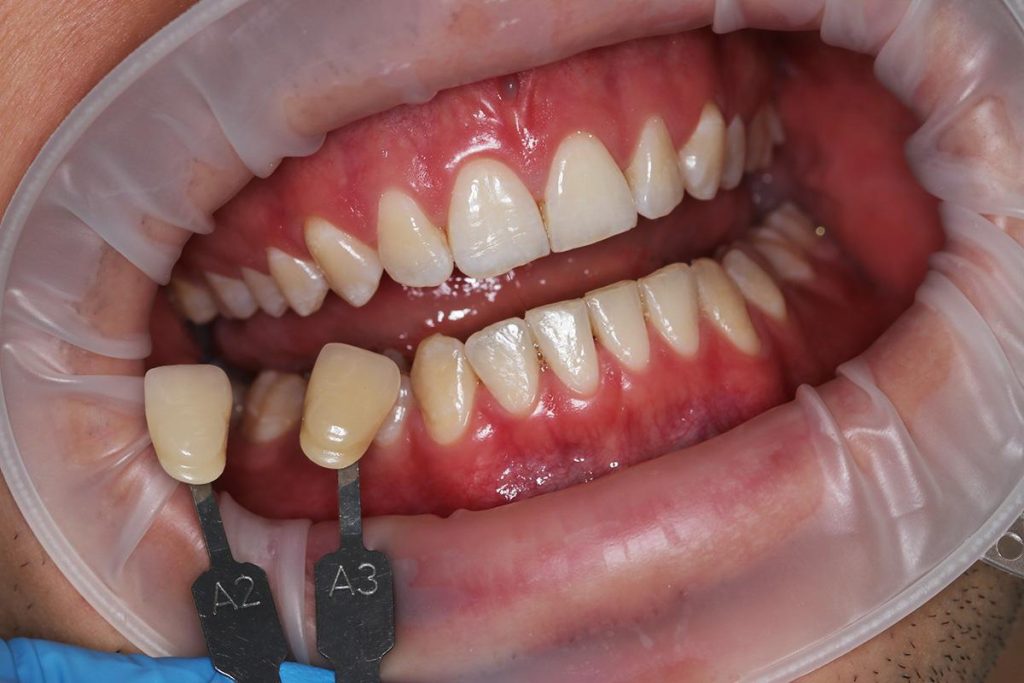

- Przeprowadziliśmy wybielanie zębów, aby uzyskać idealny odcień.

- Wykonaliśmy pełnoceramiczne licówki na górne jedynki.

- Zmieniliśmy wygląd kła przy pomocy licówki, aby wyglądał jak naturalna dwójka.